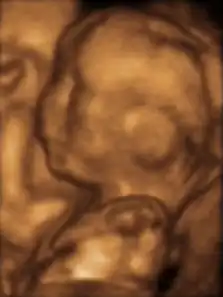

Le diagnostic de RCIU est le plus souvent évoqué devant la découverte d'une hauteur utérine insuffisante pour le terme. Cette hypothèse de RCIU doit être distinguée du petit poids pour l'âge gestationnel[41]. Parfois, c'est au cours du bilan d'une maladie connue pour ses risques de RCIU, à l'occasion d'une échographie obstétricale systématique, au cours du bilan d'une infection materno-fœtale, etc. Le diagnostic est affirmé par la mesure des biométries fœtales : périmètre abdominal, diamètre bipariétal, périmètre crânien, longueur du fémur. La biométrie fœtale doit être comparée à la taille et au morphotype parental. L'examen recherche aussi des causes locales de RCIU (malformation utérine, grossesse gémellaire), apprécie les possibilités de croissance fœtale par l'étude doppler d'une artère ombilicale et recherche par l'étude des artères utérines les causes vasculaires en rapport avec une hypertension artérielle gravidique. L'étude soigneuse de la morphologie fœtale permet parfois de rattacher le RCIU à un syndrome malformatif. Si l'examen ne met pas en évidence d'anomalie fœtale, il faut évaluer le bien-être fœtal à un rythme qui dépend de la sévérité et du type de RCIU.

Le RCIU est fortement liée au développement cérébral minimum et à des manifestations sur le développement à long terme portant sur la capacité motrice, sur la cognition et sur l'apprentissage et le comportement. L'importance du RCIU, ainsi que l'âge gestationnel, jouent des rôles modulateurs importants dans la structure et la fonction cérébrales altérées[29]. Les premiers signes d'anomalies structurelles du cerveau RCIU peuvent être évalués par l'imagerie par résonance magnétique (IRM) ou par IRM de diffusion pendant le développement fœtal. L'IRM du cerveau fœtal au cours du développement montre un volume cérébral réduit, une modification du repliement cortical et de la morphologie du cerveau chez les fœtus RCIU[131],[132],[133].Peu de temps avant la naissance, la réduction du volume crânien est en rapport avec une diminution du volume de matière grise corticale chez les nourrissons RCIU[134] et à un profil de développement altéré de la myélinisation de la substance blanche[135], de l'hippocampe[136] et des noyaux gris centraux[137]. L'IRM fonctionnelle est également un moyen futur pour étudier les réseaux fonctionnels du cerveau entier chez les nouveau-nés, pour l'évaluation de l'organisation modifiée et la prédiction du neurodéveloppement à long terme[138],[139].